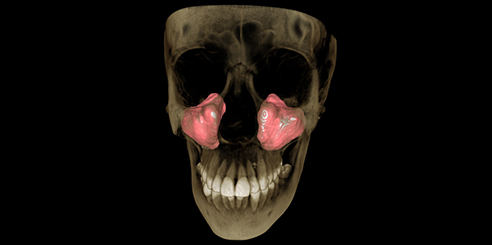

Next, Nerve Detection with Dental CBCT (AI+Nerve)

The system automatically identifies and labels the neural tube within the CT image.

This function simplifies diagnosis and supports more precise surgical planning.